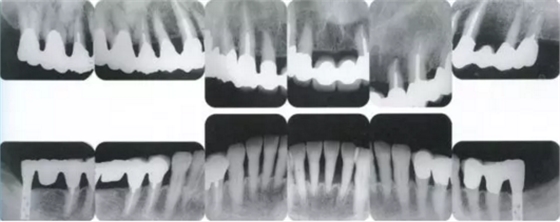

22222222222222.png

▲圖19-2,3

上下頜咬合面照。

22222222222222222222222222.png

▲圖19-4

X光片。牙槽骨明顯缺失。